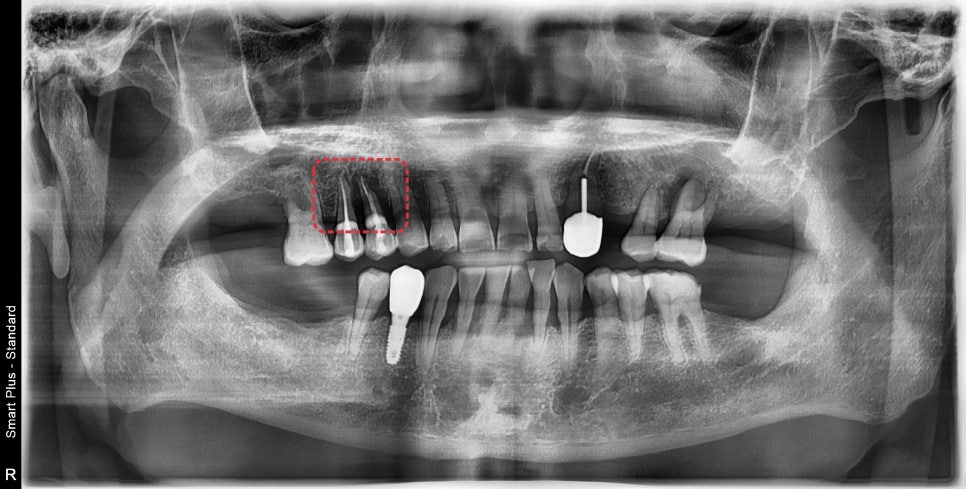

사진에 표시된 부분이 과거에 신경치료가 되어있었고

주변으로 염증이 생겨 치아를 지지해 주는 뼈가 흡수되어

치아 동요도가 관찰되었습니다.

진단 결과 발치가 필요했으나